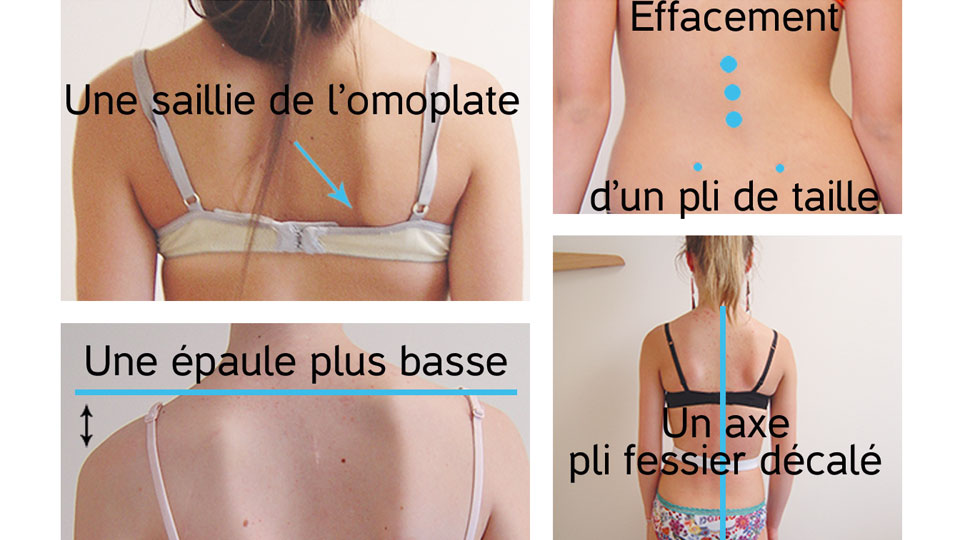

Gibbosité :

bosse produite par une déformation de la colonne vertébrale.